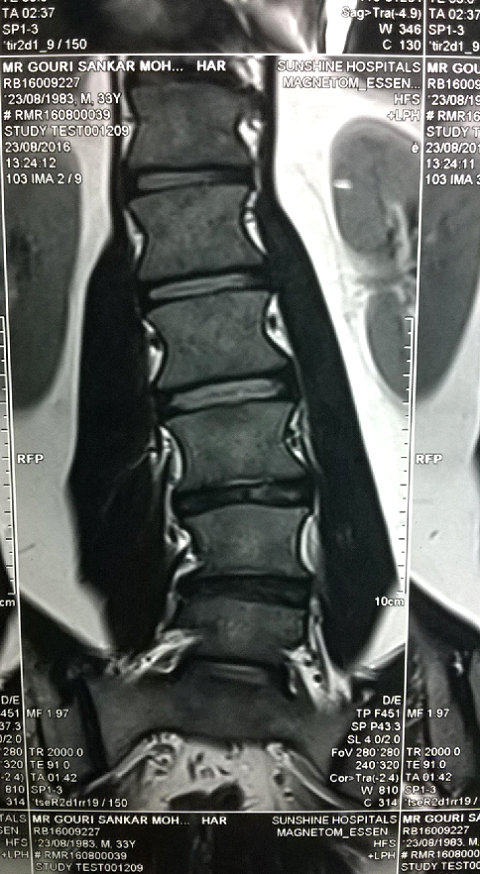

MRI of Geetanjali Behere